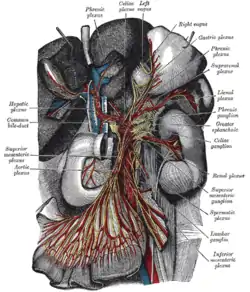

Greater splanchnic nerve, seen in thoracic cavity seen from left side. The celiac ganglia with the sympathetic plexuses of the abdominal viscera radiating from the ganglia.

The celiac ganglia with the sympathetic plexuses of the abdominal viscera radiating from the ganglia. The relations of the viscera and large vessels of the abdomen. Seen from behind, the last thoracic vertebra being well raised.